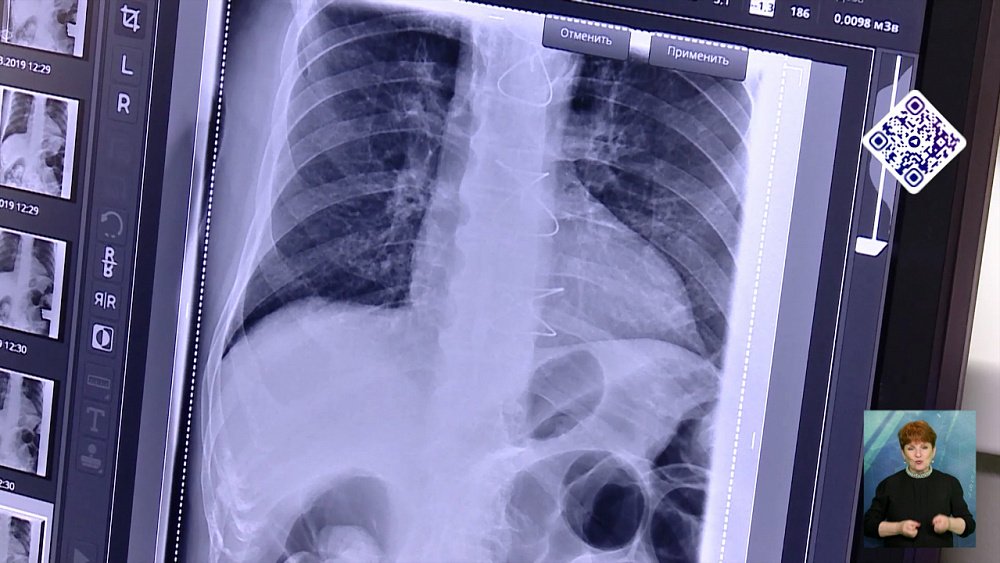

В таинственном исчезновении ювелирки пришлось разбираться полицейским из Миасса. Так как в палате мужчины лежали вдвоем, посторонних не было. Подозрения сразу пали на воришку. Стражи порядка вместе с врачами повели пациента на рентген. Там-то и выяснилось. «Золотишко» не пропадало. На 55 тысяч рублей им полакомился сосед по палате хозяина украшений. Сейчас горе-преступнику грозит уголовное наказание.

А, вот, как доставали золото — остаётся только догадываться.